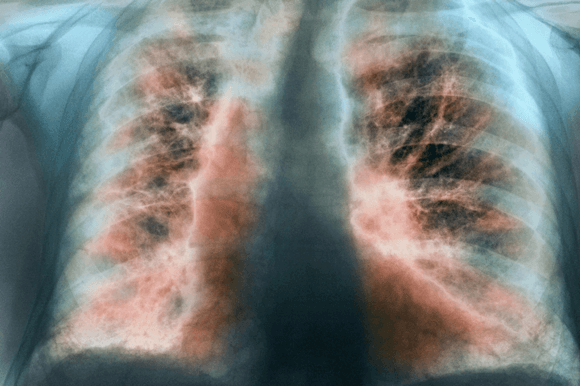

التليف الرئوي مجهول السبب

التليف الرئوي مجهول السبب IPF: الأسباب والأعراض والتشخيص والعلاج